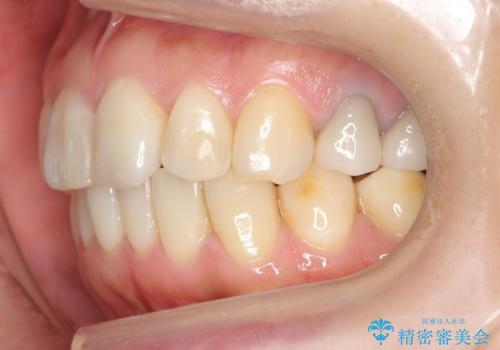

ご希望のマウスピース矯正で歯並びが綺麗になり、大変喜んで頂けました。

治療後には笑うと見えて気になっていた銀歯も白くなり、より一層素敵な笑顔を見せて下さいました。

ホワイトニング予定のため、セラミッククラウンの色は隣在歯よりやや白めにオーダーしました。

左下7欠損に関してはインプラントを検討中とのことです。

クラウンの種類:オールセラミッククラウン エコノミー(e-max press Cr)

インレーの種類:e-max press セラミックインレー